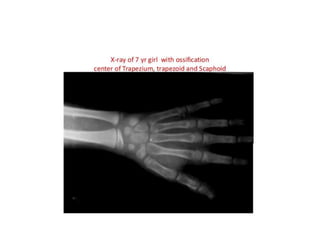

Pre-puberty

• Females: 2 years to 7 years of age

• Males: 3 years to 9 years of age

• Assessments of skeletal maturity in pre-pubertal

children are primarily based on the

epiphyseal size of the phalanges as they relate

to the adjacent metaphyses

• The epiphysis of the ulna and all carpal bones,

with the exception of the pisiform, usually

become recognizable before puberty.

• However, these ossification centers, like those

of the metacarpals, are less reliable indicators

of bone age at this stage of life.

Early and Mid-puberty

• Females: 7 years to 13 years of age

• Males: 9 years to 14 years of age

• As in pre-pubertal children, assessments of skeletal

maturity in early and mid-puberty are also based on

the size of the epiphyses in the distal phalanges (first)

and the middle phalanges (second).

• The epiphyses at this stage continue to grow and their

widths become greater than the metaphyses

• Thereafter, the contours of the epiphyses begin to

overlap, or cap, the metaphyses. This capping effect

is depicted in a two-dimensional radiograph as small

bony outgrowths, like tiny horns, on both sides of

the shaft.

• The pisiformand the sesamoid in the tendon of the

abductor pollicis, just medial to the head of the first

metacarpal, become recognizable during puberty.

• However, these centers, as well as those of the other

carpals and metacarpals, are less reliable as

indicators of bone age at this stage of development.